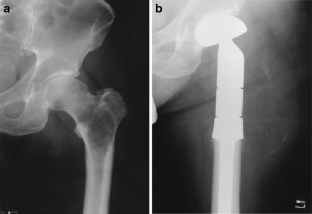

Fig. 2